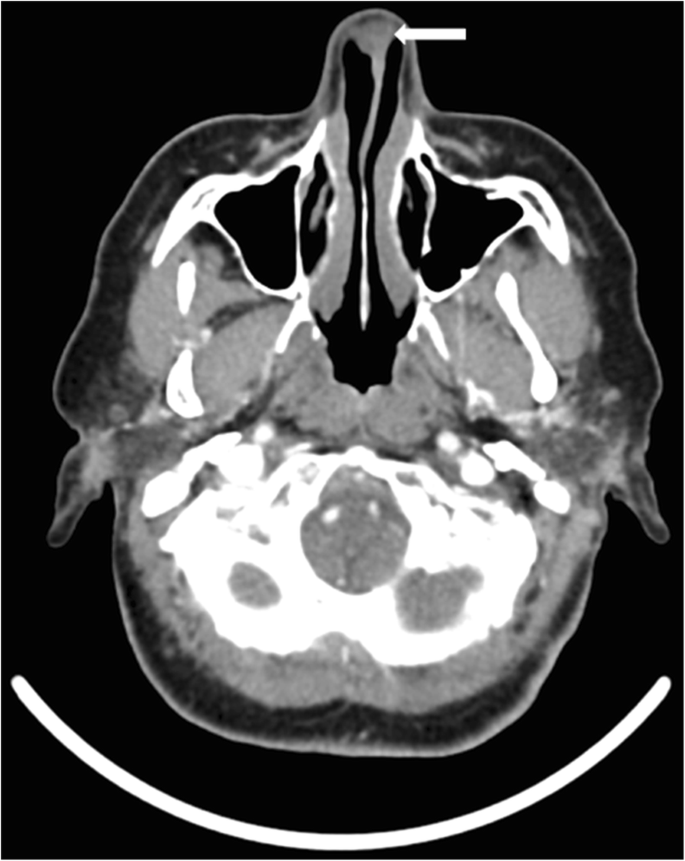

Computed tomography (CT) of the paranasal sinuses demonstrated a well-circumscribed lesion arising from the anterior cartilaginous nasal septum. The mass measured 2.2 × 1.5 × 1.0 cm and extended into the right vestibule. There was no evidence of bony erosion (Fig. 1). There was no locoregional or distant metastatic disease identified on imaging studies.

Imaging studies are essential to evaluate the osseous and soft-tissue characteristics of the tumor, as well as the extent of its growth to guide appropriate preoperative planning. The most commonly used modalities are CT and MRI. Radiographic findings may demonstrate calcification and cortical bone erosion. Chondrosarcomas typically appears as hypoattenuating matrix with the presence of scattered small, finely speckled, amorphous ring-forming calcifications (also termed “popcorn calcification”), as well as foci of associated erosion of the septum and adjacent bony structures [7, 16]. However, CT may not accurately show the full extent of soft-tissue and intraosseous involvement, and thus MRI is preferable for staging of the tumor.